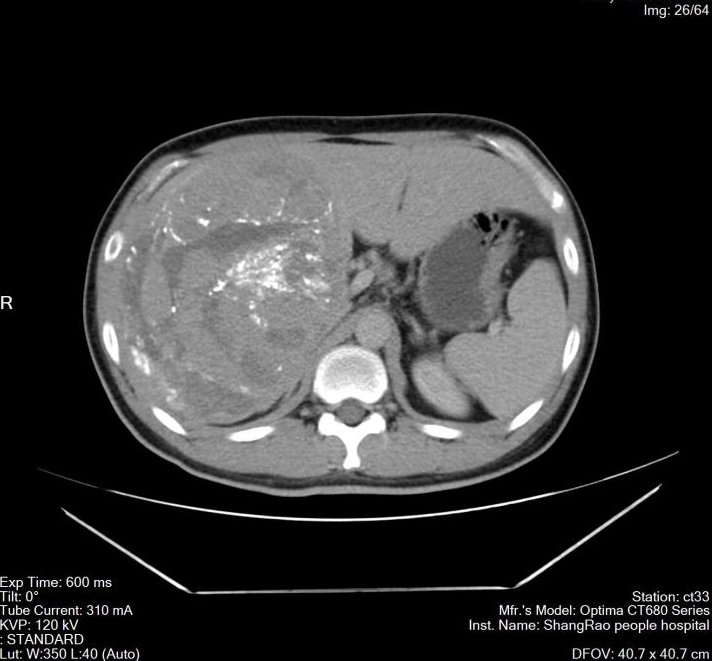

6月10日,在丁金火的周密規(guī)劃和指導下,由洪波、曾廣源、鄧高旺手術(shù)團隊及麻醉醫(yī)生、手術(shù)護士等全力配合協(xié)作,為小黃實施了術(shù)中超聲引導腹腔鏡前入路解剖性右半肝切除術(shù)。術(shù)中探查情況與術(shù)前評估基本一致,手術(shù)歷時約8個小時,出血僅100毫升。采用前入路,超聲引導下精準處理右肝流入血管后,依缺血分界離斷肝實質(zhì),不擠壓翻動腫瘤,降低癌細胞血行播散幾率,切除的腫瘤包膜完整無撕裂,重約3公斤,病理證實為中分化肝細胞癌。

手術(shù)標本